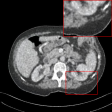

Refer to caption

(a) LDCT

(b) BM3D

(c) RED-CNN

(d) DIP

(e) LIR

(f) Ours

(g) NDCT

Figure 4: Qualitative results of our method and other baselines on Mayo Clinic Low Dose CT dataset. (a) Real low-dose. (b)-(f) Results of each methods. (g) Real normal-dose. As shown in the highlighted red box, the reconstructed image by our method has few noise and artifacts. The display window is [160,240]160240[160,240] HU.

Denoising on Low-Dose CT

Since Computed Tomography (CT) helps to diagnose abnormalities of organs, CT is widely used in medical analysis. Reducing the radiation dose in order to decrease health risks causes noise and artifacts in the reconstructed images. Like the real-world noise, the noise distributions of the reconstructed image are difficult to model analytically. Therefore, we adopt a CT dataset authorized by Mayo Clinic [Moen etย al.(2021)Moen, Chen, Holmesย III, Duan, Yu, Yu, Leng, Fletcher, and McCollough] to evaluate the generalization ability of our method on real-world noise. Mayo Clinic dataset consists of paired normal-dose and lose-dose CT images for each patient. The Normal-Dose CT (NDCT) and the Low-Dose CT (LDCT) images correspond to clean and noisy images, respectively. For the training, we obtain 2,850 images in 512ร—512512512512\times 512 resolution from 20 different patients. We construct 1,422 LDCT images from randomly selected 10 patients as a noise set and 1,428 NDCT images from the remaining patients as a clean set for unpaired training. For the test, we obtain 865 images from 5 different patients. As shown in Table 2, our method achieves the best and the second-best performance in PSNR and SSIM, respectively. Note that our model trained on the unpaired dataset outperforms the RED-CNN trained on the paired dataset in PSNR. It indicates that our method can be more practical in medical analysis where obtaining paired datasets is challenging. We also compare the qualitative results with other baselines. As shown in Figure 4, other methods tend to generate artifacts or lose details. On the other hand, our method shows a reasonable balance between noise removal and image quality. More qualitative results are provided in the supplementary material.